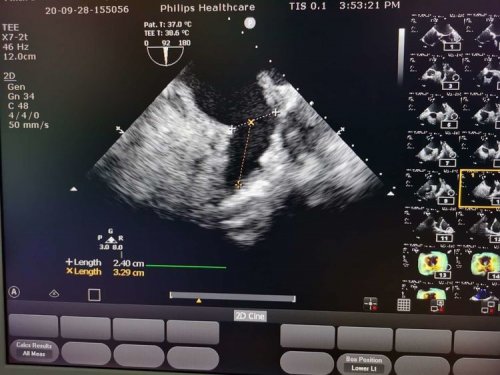

手术中,房颤消融环肺静脉完全隔离,左心耳完全封堵,手术用时仅花费3个小时,封堵和消融效果都非常完美。术后第二天徐阿姨便能下床活动,活动后无不适,并且无任何手术并发症,患者可以顺利在45天后就改变用药方案,不必再担心抗凝中断的风险。